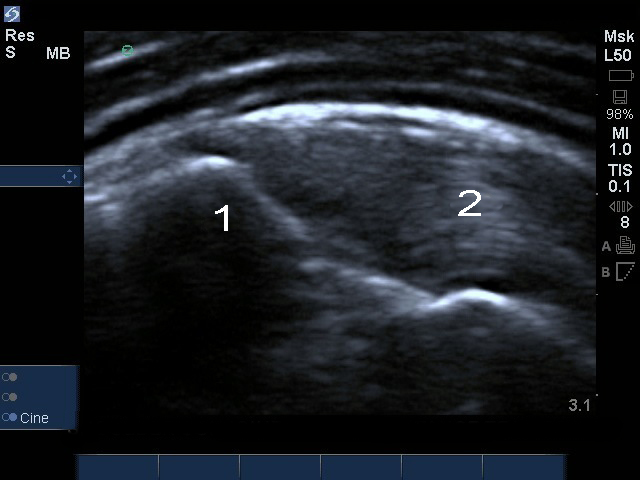

Intratendinöse Ruptur der gemeinsamen Sehnenplatte an der Schulter (ZOOM)

1. Tuberculum majus

2. Supraspinatus